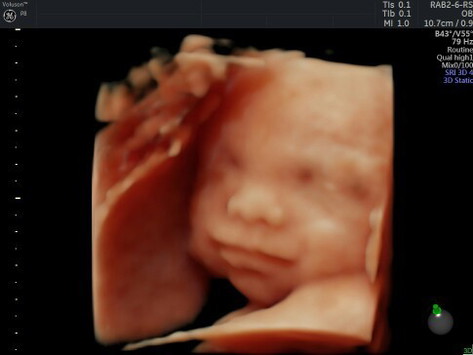

masyaallahh tabarokallah.. sudah msuk 19 minggu 6 hari. kedutan masih halus pas usg ternyata aktif banget. sampe pas video manyun manyun lagi ngempeng juga dd nya.. sayangnya JK msh ketutupan betis jd belum bisa dpastikan takutnya meleset kata dokter. bunda bunda yg HPL september 2021 udh ngerasain apa aja.?? #bantusharing #firstbaby #1stimemom sharing yuk